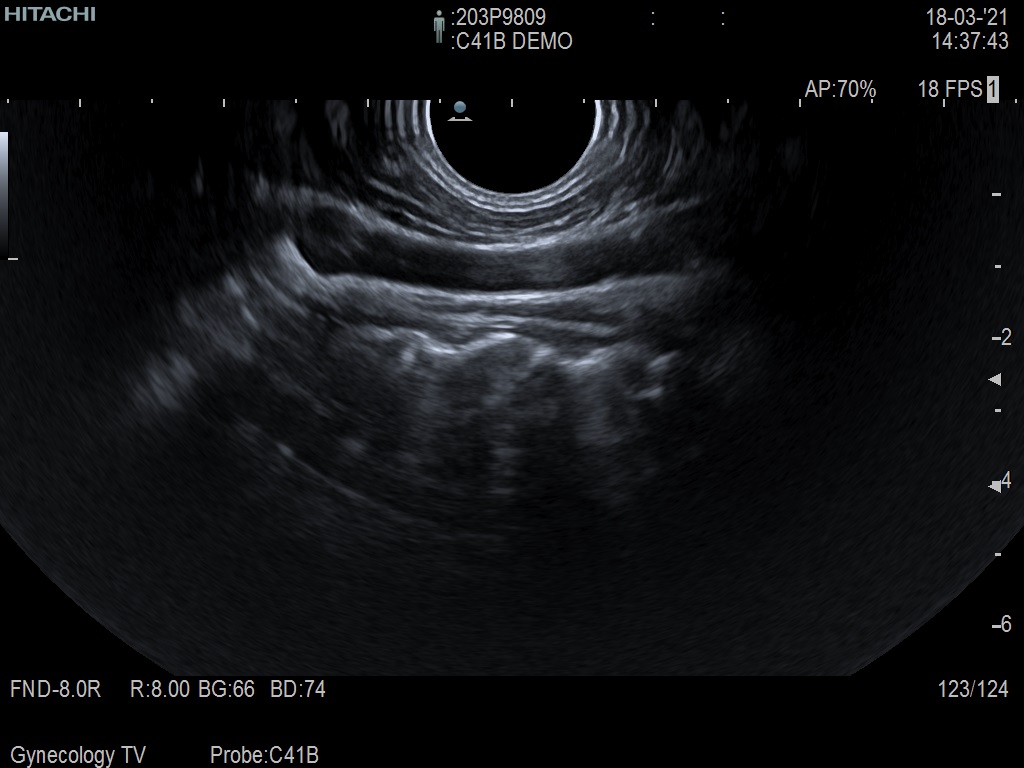

Hitachi C41B DEMO Endocavity Vaginal – ARIETTA

ARIETTA Endocavity C41B

Angled End-fire Endocavity

Hitachi C41B Endocavity Vaginal – ARIETTA

Frequency Range: 10 – 2 MHz

Scan Width: 10 mm Radius

Scan Angle: 200° FOV

Hitachi C41B Endocavity Vaginal/Rectal – ARIETTA for Angled End-fire Obstetric, Gynecology and Endorectal

| Ακτινολογικές λειτουργίες | Contrast Harmonic Imaging (CHI), Elastography (RTE), RT Sonography (RVS) |